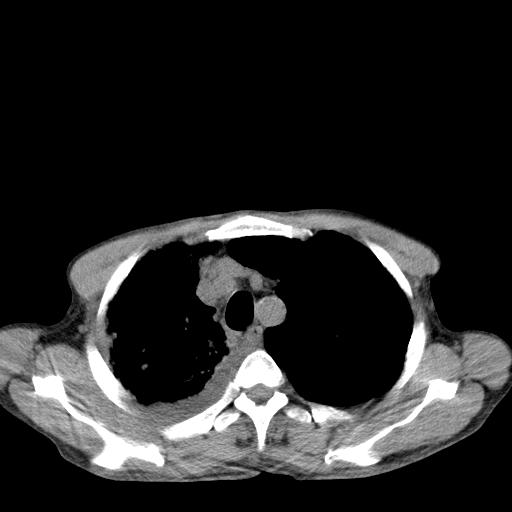

男性 75  咳嗽 一周前发热最高达39

右肺继发型tb并右侧tb性胸腔炎,右侧胸腔大量积液并右下肺膨胀不全,慢支肺气肿、多发肺大泡。建议抽胸水实验室检查并复查排除恶性在占位。

右上肺继发型肺结核,右胸腔中等量积液。

左上肺大泡。

结核的基础上有纵隔淋巴结肿大,右侧有胸水,但右侧纵隔反而窄,说明有肺有不张。

再就是右下肺有块影,和不张混合,还是不能除外肺癌。

1)右肺继发型肺结核。2)左肺胸膜下多发性肺大泡。3)右侧胸腔积液。